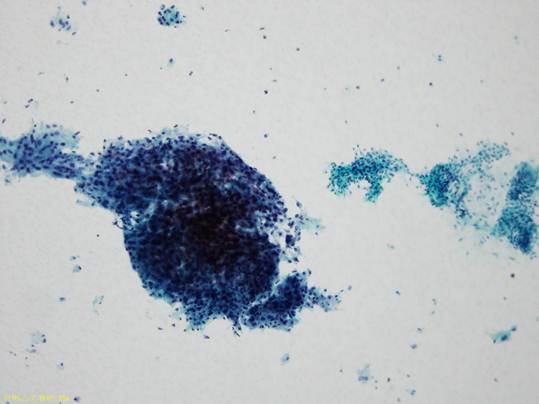

細胞診所見

比較的きれいな背景を伴って上皮様細胞と紡錐形細胞からなる多形腺腫と考えられる集塊をみとめる。